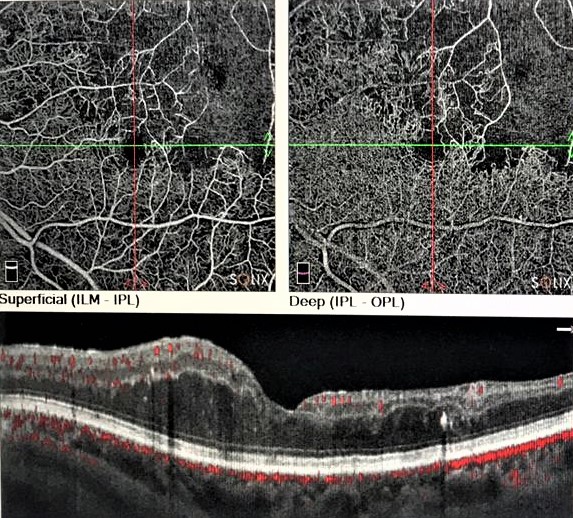

Комбинированное лечение неоваскулярной глаукомы на фоне тромбоза центральной вены сетчатки (клинический случай)

Цель. Представить особенности клиники и оценить эффективность лазерного и хирургического лечения пациентов с неоваскулярной глаукомой на фоне перенесенного тромбоза центральной вены сетчатки.

Материал и методы. Обследованы два пациента с вторичной неоваскулярной глаукомой вследствие тромбоза центральной вены сетчатки. Выполнены оперативные вмешательства: пациенту М. - микроимпульсная циклофотокоагуляция (дважды), интравитреальное введение ингибитора ангиогенеза (5 инъекций), лазеркоагуляция сетчатки (двухэтапная); пациенту Е. - микроимпульсная циклофотокоагуляция, интравитреальное введение ингибитора ангиогенеза (2 инъекции), имплантация клапана Ahmed.

Результаты. В результате проведенного лечения была достигнута компенсация внутриглазного давления, улучшение зрительных функций, снижение неоваскуляризации структур переднего отрезка глазного яблока.

Обсуждение и заключение. Микроимпульсная циклофотокоагуляция может применяться в комплексном лечении неоваскулярной глаукомы на любом этапе с целью снижения ВГД и уменьшения неоваскуляризации радужки и структур угла передней камеры в послеоперационном периоде.